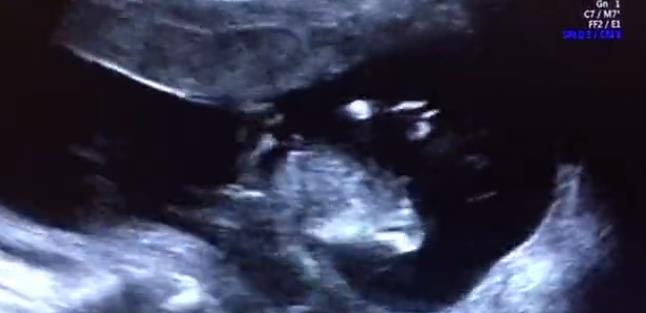

最后,我們再和大家分享兩段

我院四維篩查雙胞胎超聲影像

兩段篩查視頻都是超聲科孫輝醫生

通過E10四維設備為雙胎寶媽進行的

其中一位是不孕科治療后迎來好孕

而另一位則是產科的產檢分娩客戶